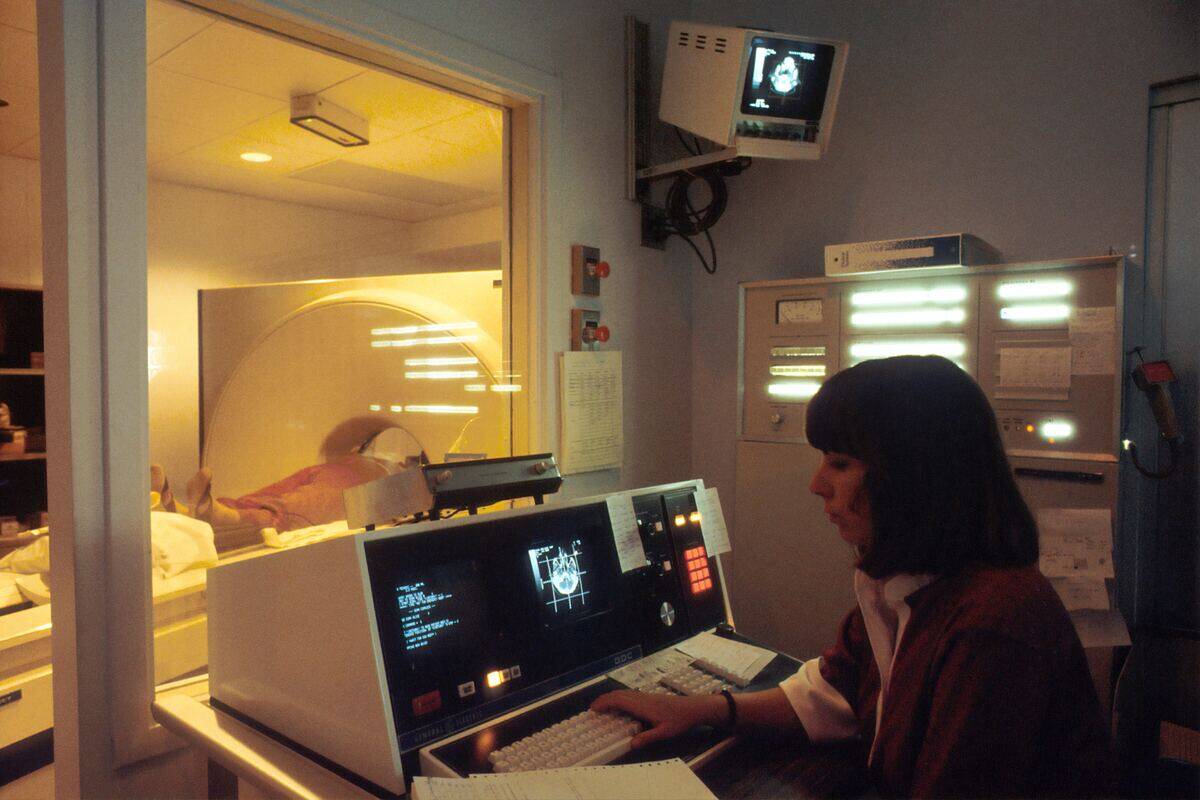

Doctors performed CT scans on the young girl's skull and were shocked to discover a four-inch parasitic fetus within her brain.

Once the CT scans revealed the existence of her twin that was pressing against her brain, doctors knew they had to remove it immediately. By the time they were able to extract it, it had been growing inside the girl's skull for months, long enough for it to develop bones, organs, and limbs.